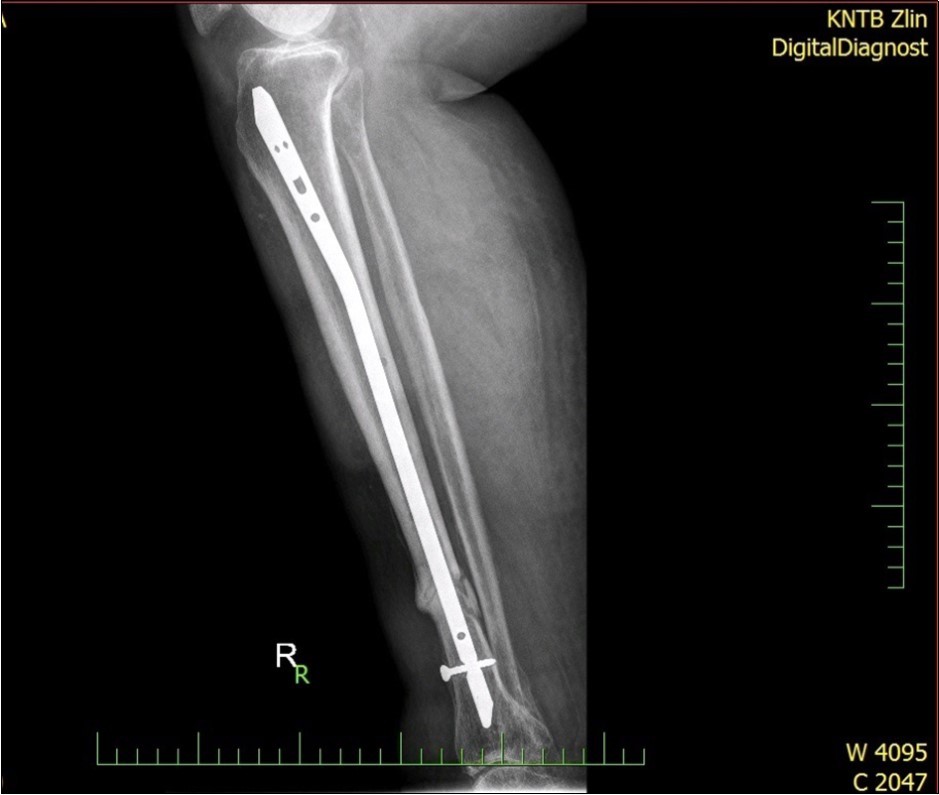

Figure 28.23 April. Surgery conversion of osteosynthesis. Removal external fixator and implantation intramedullary tibial nail. Gradual bone healing - last X-ray september 2019

Figure 29.23 April. Surgery conversion of osteosynthesis. Removal external fixator and implantation intramedullary tibial nail. Gradual bone healing - last X-ray september 2019